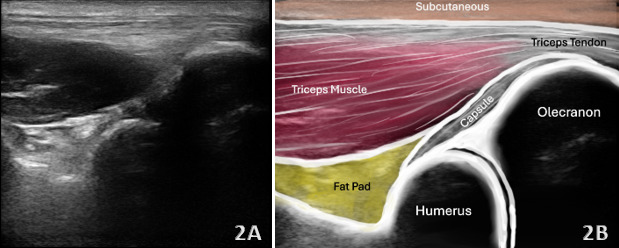

The triceps tendon is responsible for extension of the elbow during upper extremity functional activities that require the motion of pushing. Accurate diagnosis of tendon partial tears or ruptures is essential for appropriate treatment planning and optimizing patient outcomes. Diagnostic musculoskeletal (MSK) ultrasound offers a portable, real-time, and cost-effective alternative that is gaining traction in rehabilitation and sports medicine settings. MSK ultrasound has emerged as a valuable, non-invasive imaging modality for evaluating triceps tendon injuries including partial and complete tears, tendinopathy, and calcifications of the triceps insertion onto the olecranon, and even avulsions from the olecranon. MSK ultrasound is adept at detecting changes in tendon tissue composition and integrity, including both tendinopathies and partial thickness tears. Furthermore, this manuscript will review the utility of MSK ultrasound in evaluating the triceps injury, including its anatomy, common injury patterns, sonographic techniques, and clinical implications for professional rehabilitation. Diagnosis of acute injury by physical examination is often challenging and is frequently misdiagnosed. By integrating MSK ultrasound into clinical practice, providers can improve the accuracy of diagnosis, enhance diagnostic confidence, monitor healing progression, and guide rehabilitation strategies to optimal patient outcomes.